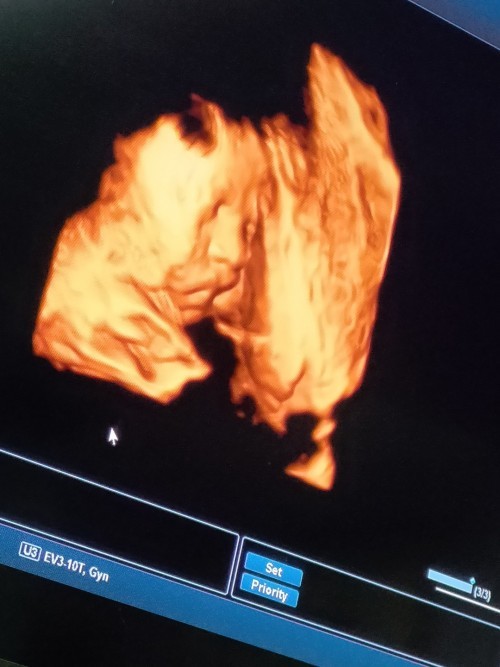

ไม่ให้เห็นหน้าเลยค้ะ ซาวตอน29วีค